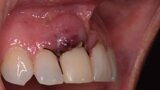

Figura 6. A pesar del defecto óseo, siempre buscamos la posibilidad de crear un nuevo alveolo quirúrgico que emerja por la zona del cíngulo de los dientes adyacentes, es decir, el margen de emergencia adecuado. En estos defectos, intentamos siempre el anclaje en profundidad con implantes largos de unos 16 mm debido al gran defecto existente. Es la única forma de que la estabilidad primaria del implante permita realizar una Prótesis Inmediata.